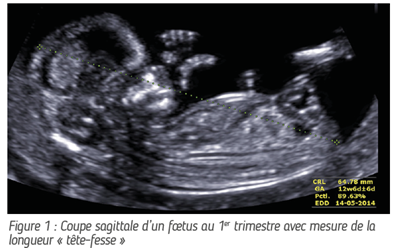

• L’examen du 1er trimestre (+/- 12 SA) peut être combiné au dépistage des anomalies chromosomiques et au dépistage de la prééclampsie (réf. 1, fig. 1 & 2). En Belgique, le dépistage des anomalies chromosomiques comme la trisomie 21 est réalisé via le NIPT (Non Invasive Prenatal Testing). Celui-ci est remboursé depuis juin 2017.